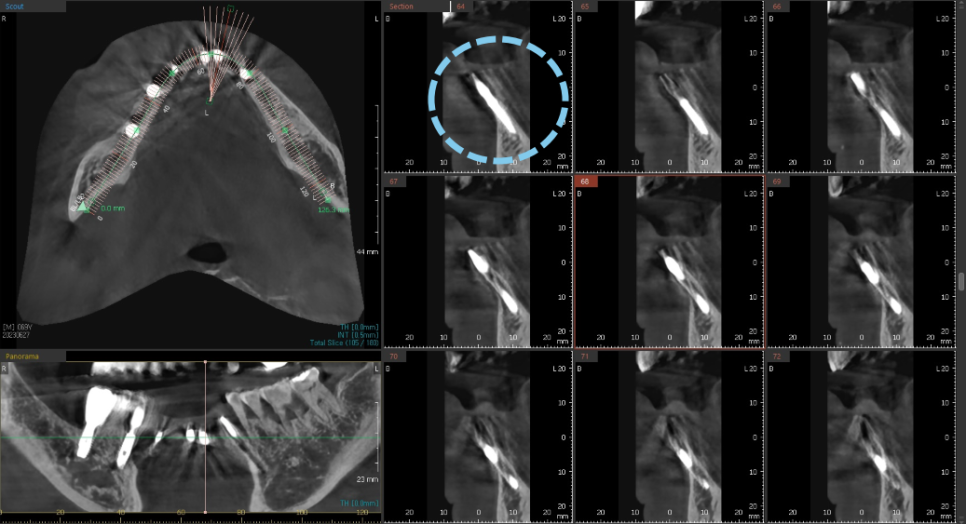

발치 후 염증으로 인해 대다수 소실된 뼈 부분을 보면

아주 얇고 경사가 심한 포인트라

임플란트를 심을 길을 내는 것도

아주아주 어려운 일입니다.

발치와 동시에 식립하는 임플란트는 정밀함을 요합니다.

앞니의 경우라면 더더욱 세심한 분석과 위치 선정이 중요하고

통상적으로 염증이 많은 부분을 깨끗하게 제거 한 뒤

뼈이식과 함께 임플란트를 하는

앞니 임플란트 술식은 매우 고난이도에 속합니다.

노란색으로 표시된 곡선의 움푹 들어간 부분이

실제로 수술시에 육안으로 잘 보이지 않기 때문에

손으로 만져보면서 조심스럽게 진행해야합니다.

또 너무 뒷쪽으로 식립하게 되는 경우

파란색 선 뒷쪽에 위치한 혀쪽의 설동맥과 가까워지게 되는데

설동맥을 건드린 경우는 대량의 출혈이 일어나게 됩니다.